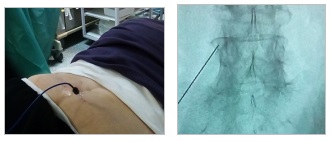

- Επισκληρίδιες εγχύσεις

- Εγχύσεις και απονεύρωση των αρθρώσεων της σπονδυλικής στήλης

- Δισκοπλαστική με χρήση laser

- Νευροδιέγερση νωτιαίου μυελού και περιφερική νευροδιέγερση